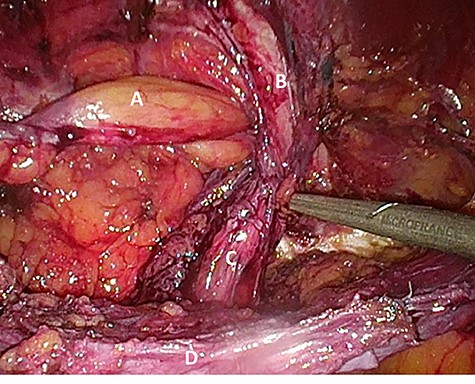

Considering the patients’ comorbidities (obesity, Type 2 diabetes mellitus), a re-TAPP was performed to avoid possible wound complications. The recurrent hernia was presumably confirmed as a lateral inguinal hernia. After dissecting dense fibrotic scar tissue around the previous mesh preperitoneally, the hernia sac was released. A large spermatic cord lipoma was found and dissected (Figs 1 and 2). A new mesh (BARD® 3D Light Mesh, 10 × 15 cm) was inserted.

Dissection of the large spermatic cord lipoma with attached fibrotic tissue.